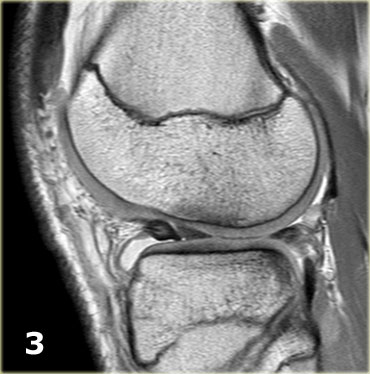

Hãy quan sát hình ảnh bên trái và cố gắng xác định vấn đề của sụn chêm này là gì.

Sau đó tiếp tục xem các hình ảnh liên tiếp tiếp theo của cùng bệnh nhân này.

Như bạn đã đoán được qua tiêu đề của đoạn này, đây là một trường hợp sụn chêm lật (flipped meniscus).

Sụn chêm lật là một dạng đặc biệt của rách dạng quai xô (bucket-handle tear).

Sụn chêm lật xảy ra khi mảnh vỡ của sừng sau bị lật ra phía trước, khiến sừng trước của sụn chêm có vẻ to hơn bình thường.

- Sừng sau quá nhỏ và sừng trước có vẻ to hơn với đường viền không đều.

- Thoạt nhìn có vẻ như có một đường rách dọc ở sừng trước, nhưng thực chất phần sau của cấu trúc này chính là phần lật của sừng sau bị rách.

Cấu trúc phía trước là sừng trước.

Cũng cần lưu ý tình trạng phù tủy xương khu trú và dấu ấn lõm sụn khớp. - Cấu trúc phía trước là sừng trước.